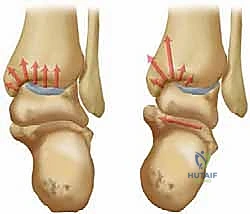

في حالة التشوه التقوسي (Varus Deformity)، يحدث ميلان في المحور الميكانيكي للساق. تخيل أنك تقود سيارة وإطاراتها غير متوازنة (Misaligned). سيؤدي ذلك إلى تآكل جانب واحد من الإطار بسرعة أكبر بكثير من الجانب الآخر. هذا بالضبط ما يحدث في الكاحل التقوسي؛ حيث ينتقل محور تحمل الوزن (Weight-bearing axis) بشكل غير طبيعي نحو الداخل (الجانب الإنسي). هذا التركيز المفرط للإجهاد يفوق قدرة الغضروف على التحمل، مما يؤدي إلى تشققه، تآكله، وفي النهاية تلامس العظم بالعظم، وهو ما يسبب الألم المبرح والالتهاب.

تكمن المشكلة الأساسية في خشونة مفصل الكاحل من النوع التقوسي في تركز الإجهاد على الجانب الإنسي. هدف جراحة قطع العظم التي يجريها الدكتور هطيف ليس فقط إيقاف هذا التدهور، بل وإعطاء الجسم فرصة لإصلاح عيوب الغضروف جزئياً عن طريق تشكيل نسيج غضروفي ليفي (Fibrocartilage) بمجرد إزالة الضغط الميكانيكي عنه.